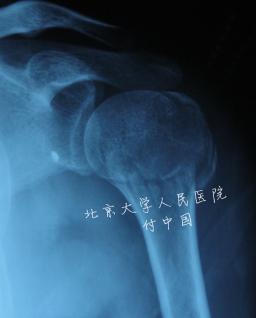

| 说明: | 一部分骨折,即使有多条骨折线,但骨折块间的移位小于1cm或成角小于45°,称为一部分骨折 |

| 标题: | 一部分骨折 |